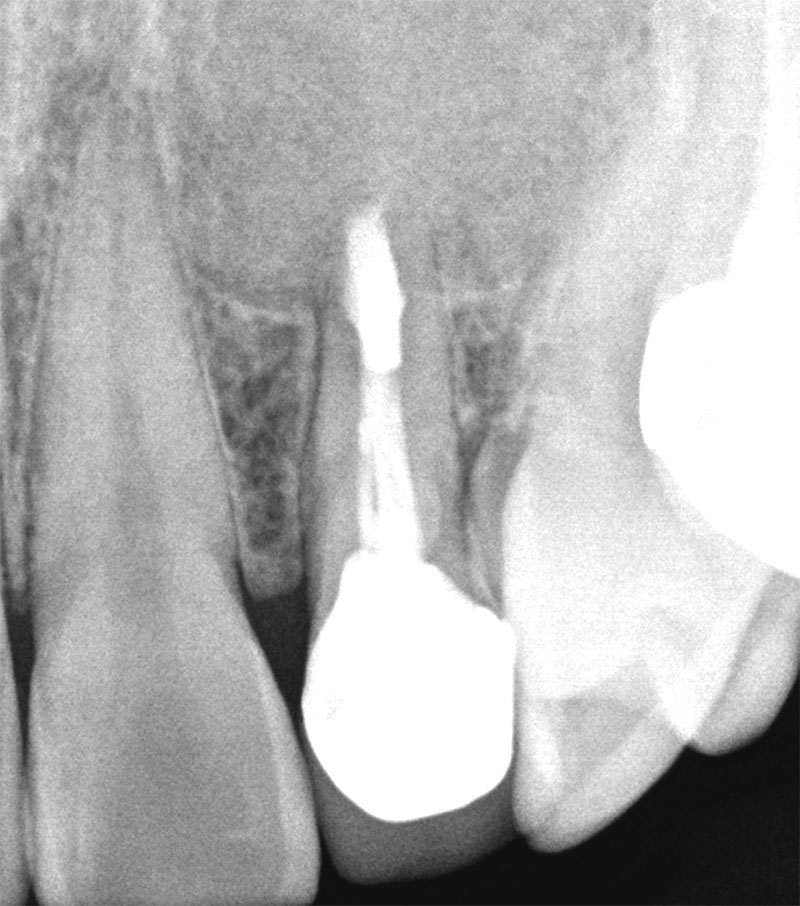

치료 1년 반 후